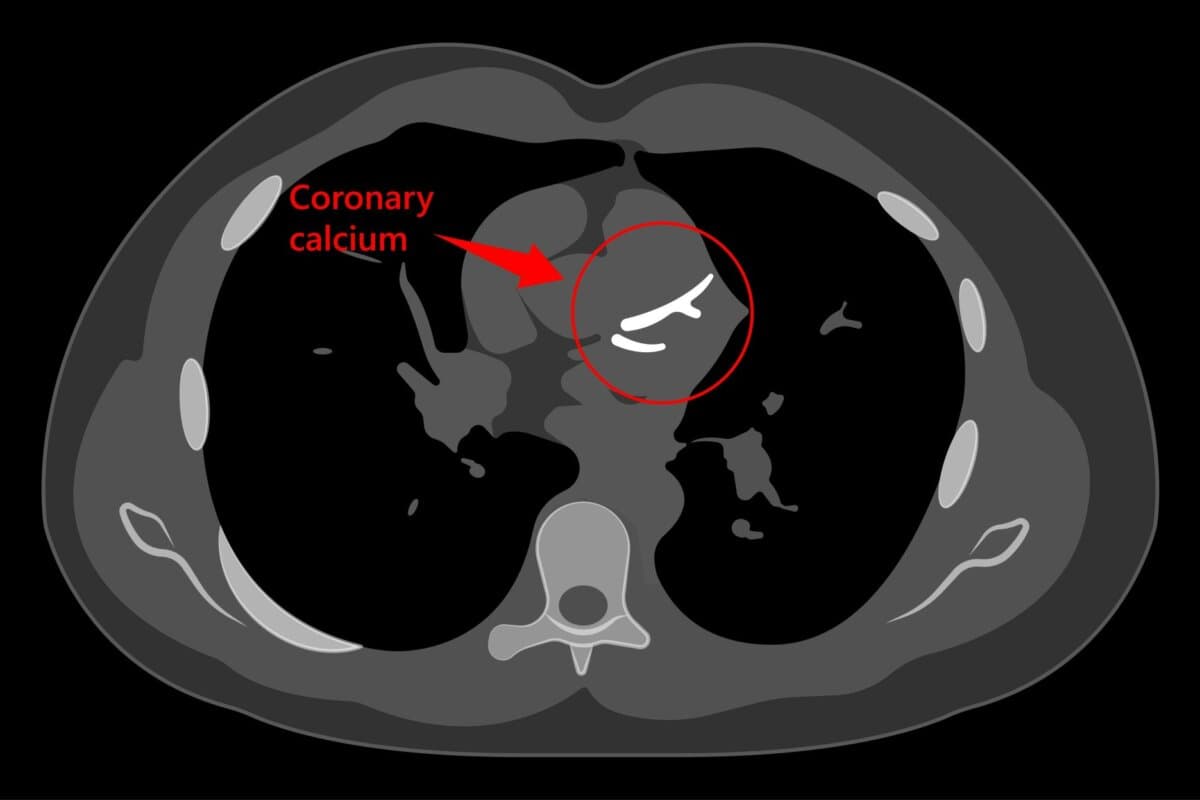

Der Grad der Verkalkung in den Herzkranzgefässen bzw. Kalzium-Score lässt sich unabhängig vom Alter als zuverlässiger Risikomarker für koronare Ereignisse heranziehen. Das ist das Ergebnis einer US-Studie.

In der retrospektiven Studie war ein koronarer Kalzium-Score von null auch bei älteren Personen mit einem geringen Risiko für ein kardiales Ereignis und mit einer niedrigen Gesamtmortalität verbunden.

Zur Quantifizierung des Risikos unterzogen sich 40.820 Patienten mit erhöhtem Koronarrisiko einem PET-CT-Scan. In der Gesamtgruppe hatten 8.179 Patienten einen Koronararterien-Kalzium-Score von Null. Die meisten (5.185) waren unter 65 Jahre alt.